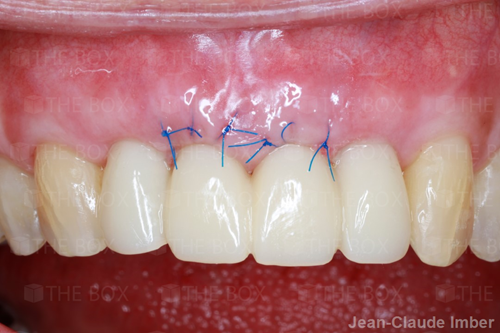

A new case was made public by Jean-Claude Imber check it out here.